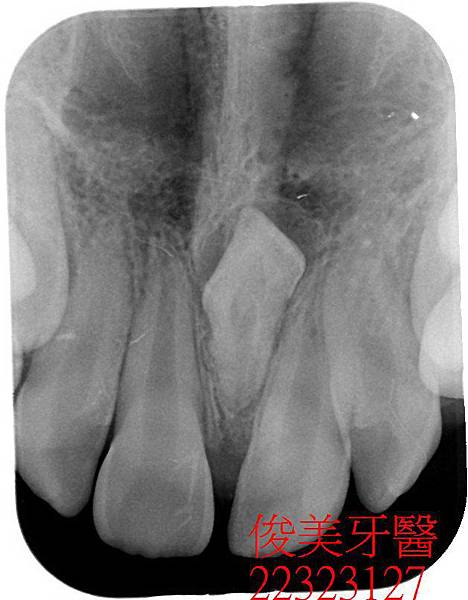

在醫師的建議下已將門牙中間的多生牙做手術性拔除....並待傷口癒合..

經拍照記錄原始狀況..

患者的上顎犬齒也一直長不出來。